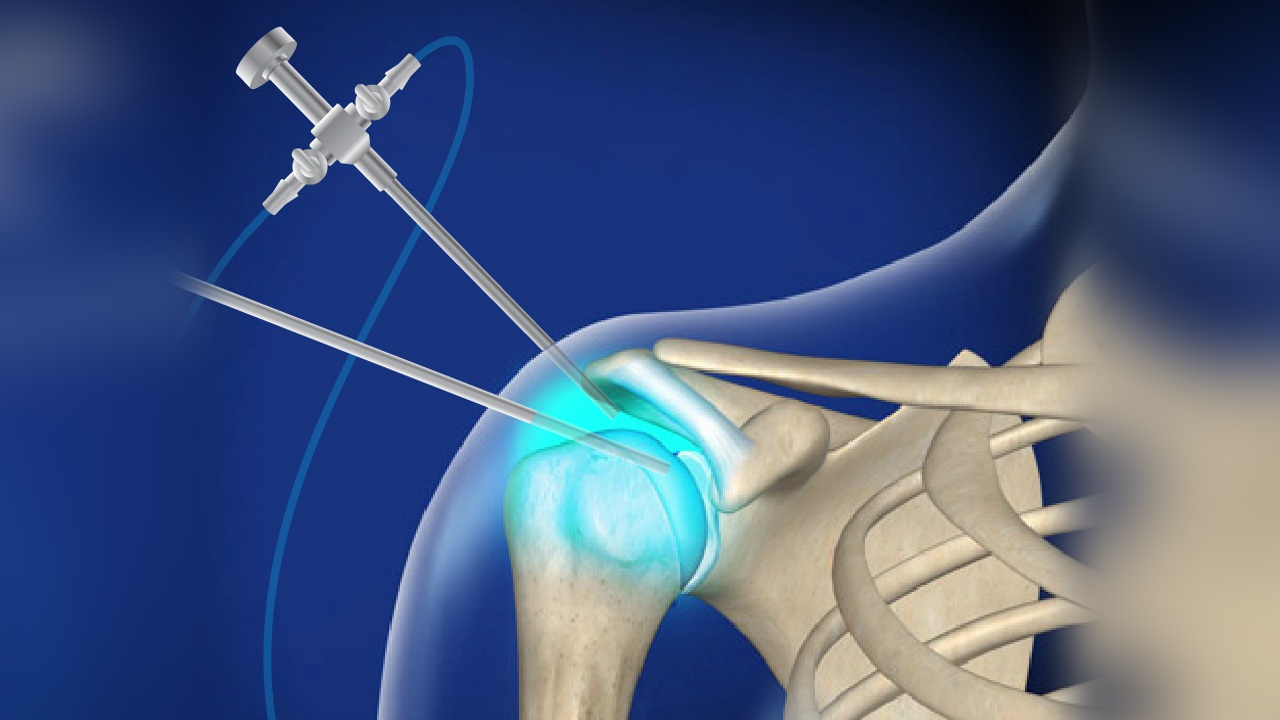

Hip fracture surgery is considered a very important procedure, as it can cause serious disruptions in the patient’s daily life. Imaging techniques are used to determine the location of the fracture before treatment. Conservative (non-surgical) treatment can be followed in cases of stable injuries, helping to reduce pain until recovery is achieved.

Surgical treatment that requires immediate correction may be used in some cases to avoid joint damage. The recovery process can take several months, and physical therapy can help alleviate pain and improve the overall condition. Regardless of the treatment method, it is important to ensure adequate rest throughout all stages of hip fracture treatment.

Hip fracture surgery may seem challenging, but it is considered a suitable treatment option for fractures in the hip area. The patient should see a doctor immediately to determine the appropriate treatment method and realign the fractured bones to their natural position. This can be done through either an incision in the hip area or by inserting screws or metal plates. Patients can typically leave the hospital after about two weeks, and complete recovery may take from 3 to 6 months.